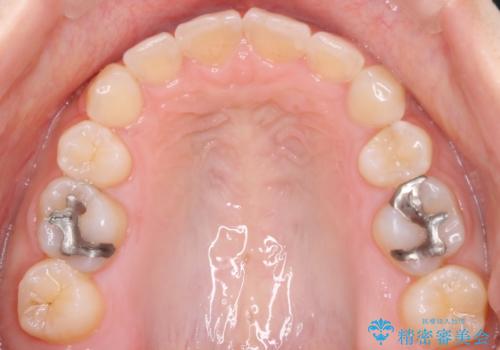

- 口元が出てるのが気になるとのことで来院されました。

上下左右前から4番目の歯を抜歯して前歯を後方に下げて、口元を下げる計画としました。

口元を大きく改善したい場合は抜歯が必要となることが多いです。